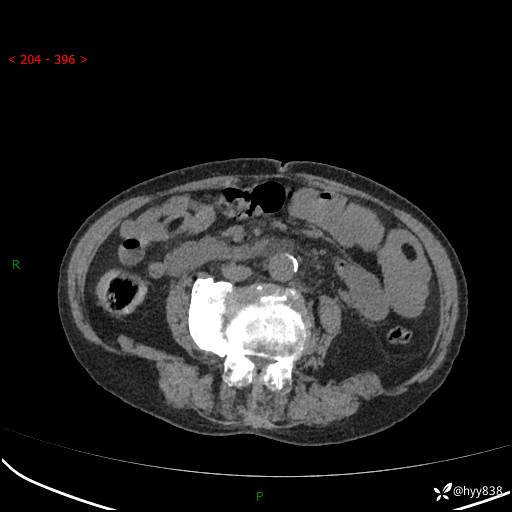

全腹部CT平扫